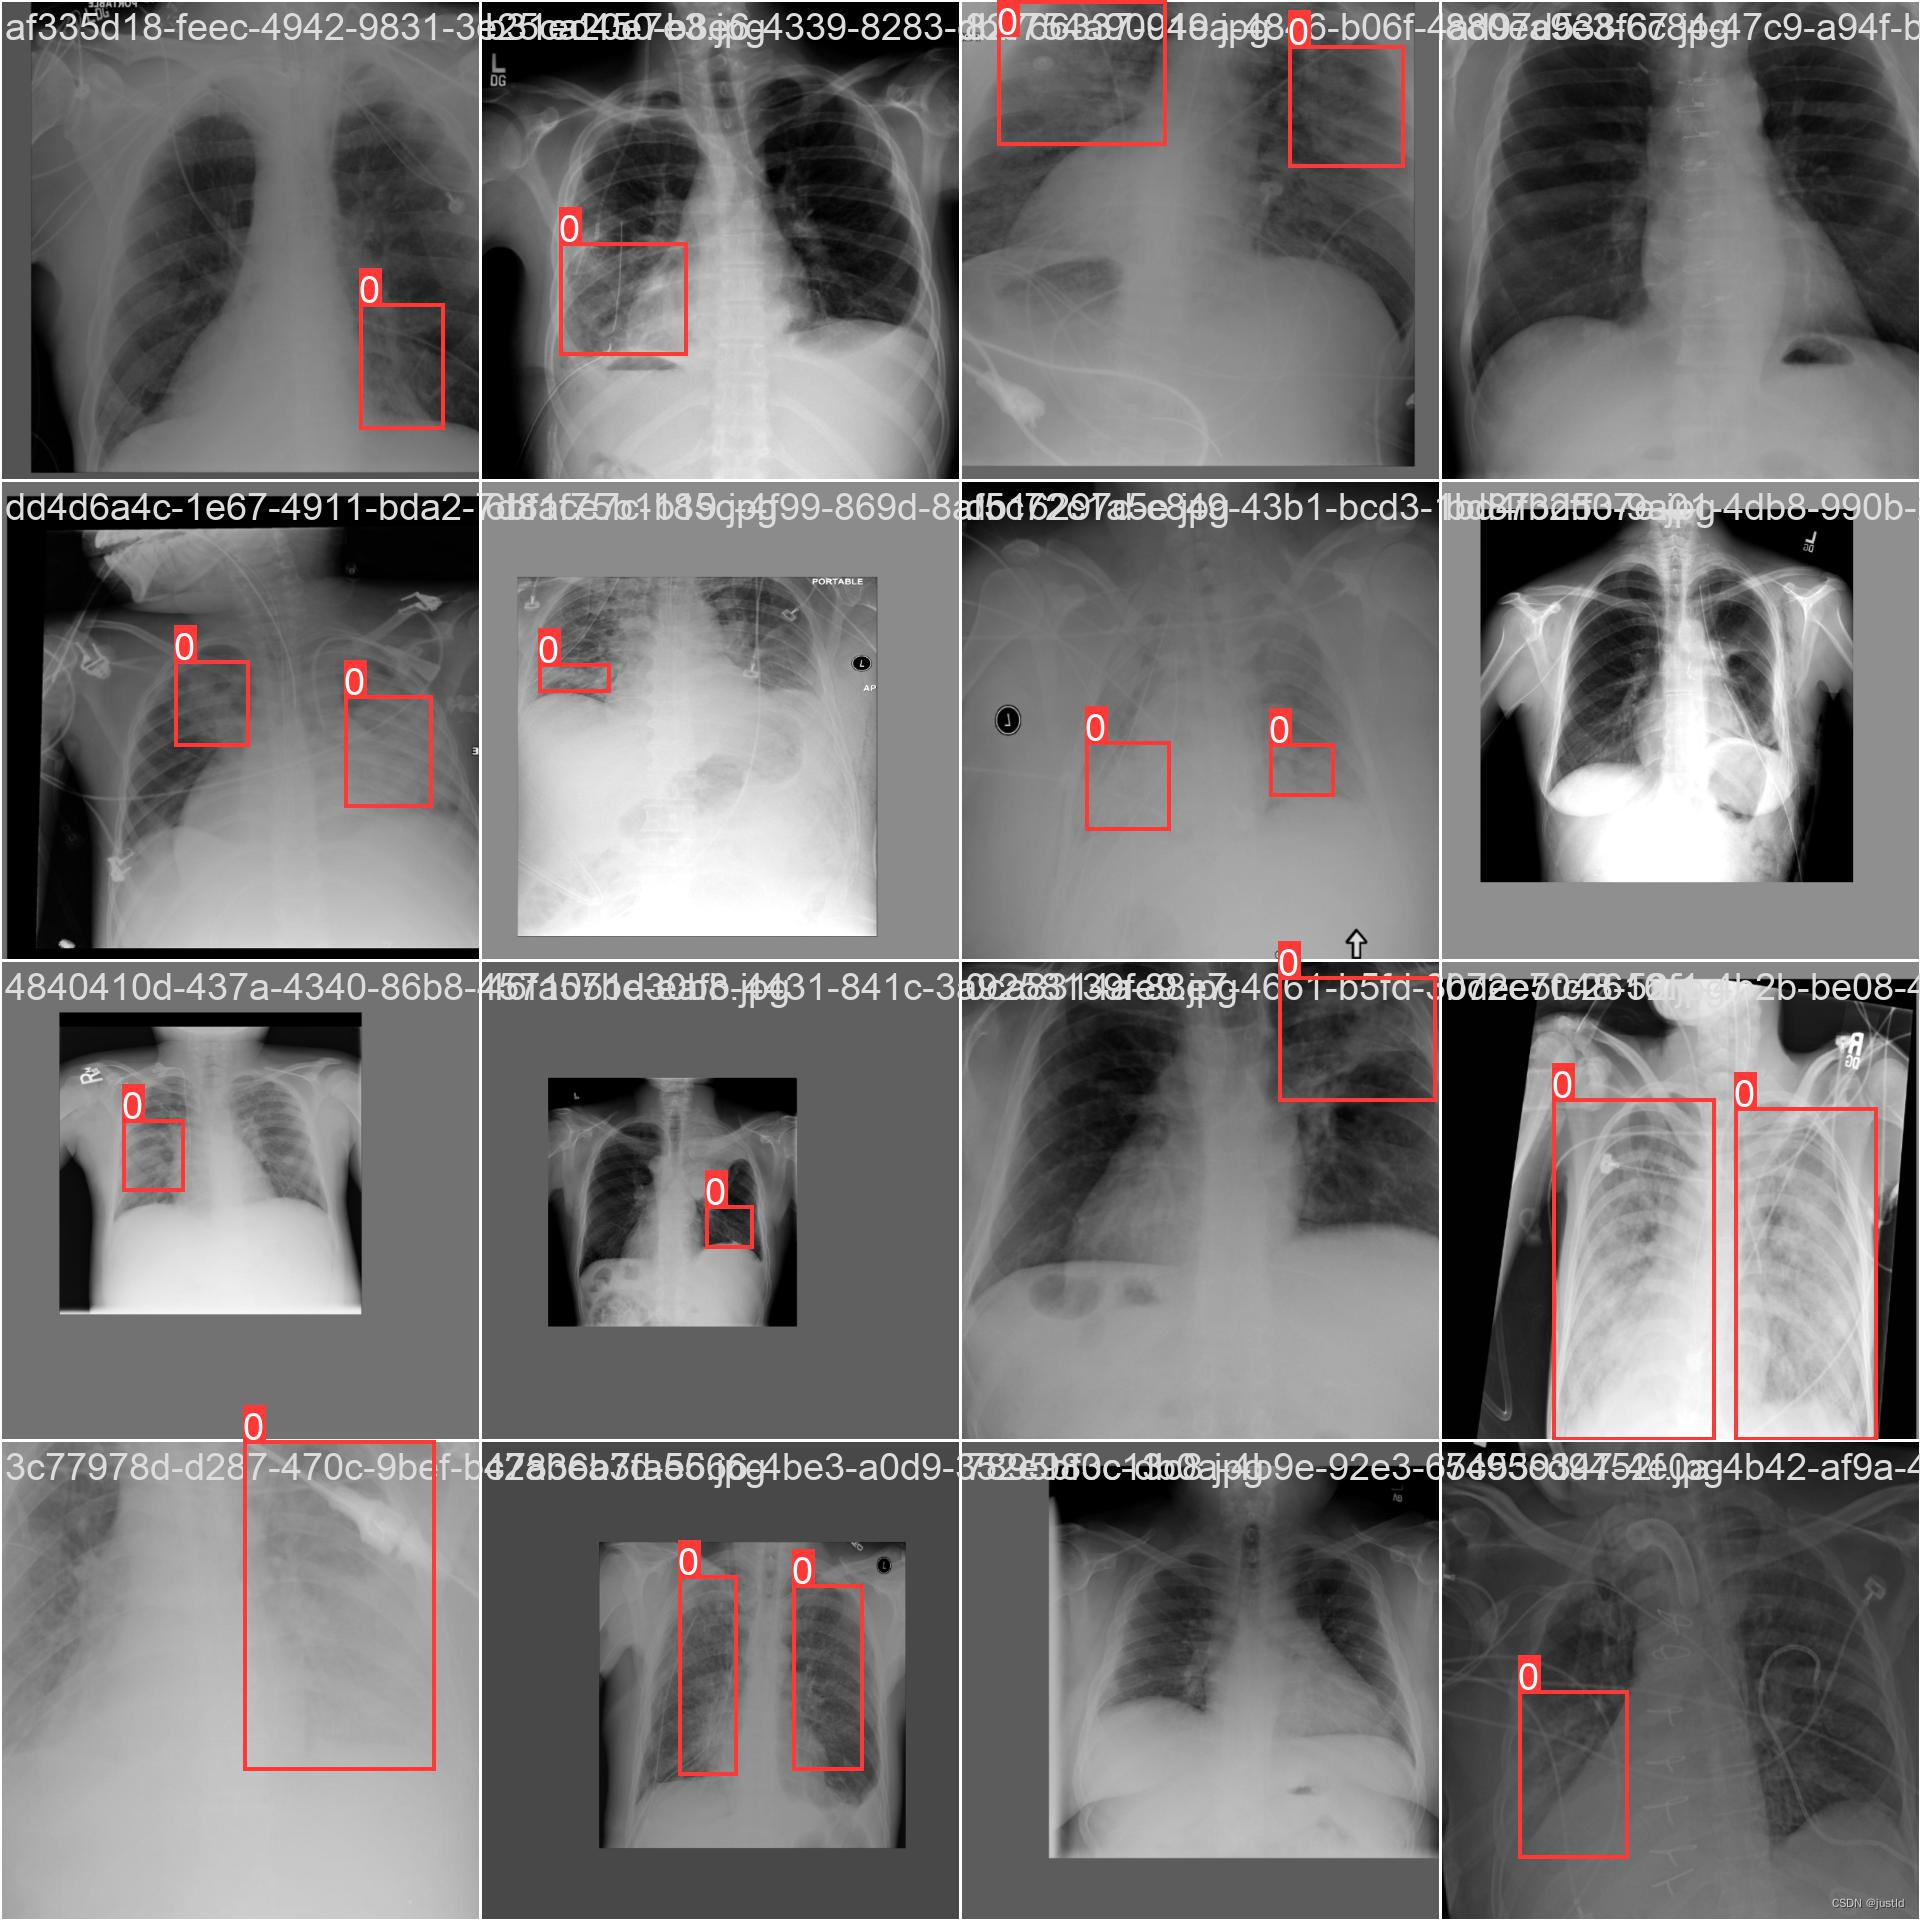

检测结果如下图:

该数据集包含5950个训练数据,662个测试数据,数据如下图: